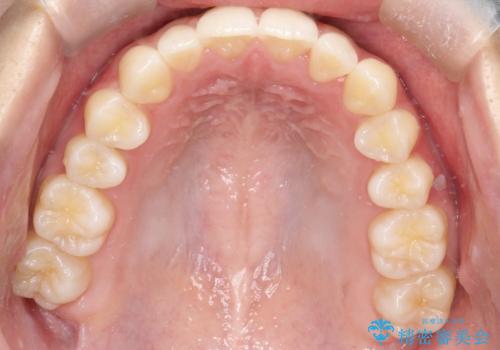

初診時の歯並びの状態としては、上下ともに全体に及ぶの中等度のがたつき(叢生)があり、全特に左上の前歯は1本だけ引っ込んでいる状態でした。

抜歯は行わず上顎の奥のスペースを利用して歯をスライドする方法の他に歯列弓の拡大やディスキング(歯と歯の間の隙間を作る処置)を行い叢生を改善しました。

歯の大きさの不揃いが原因の正中のズレは、ディスキング量を調整することで合わせています。

上の歯を後ろに送る方法として、歯茎に入れた小さなネジからゴムかけをして歯列全体を後ろに引っ張りました。

見た目、嚙み合わせ及び、治療期間や施術内容に大変ご満足いただきました。